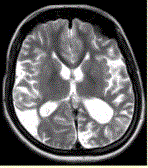

问题 女性,22岁。癫痫发作及智力异常。MRI显示见下图。 为进一步明确诊断,下一步的影像学检查首选

选项 A.MRI增强 B.FLAIR C.DWI D.MRA E.MRV F.DSA

答案 D